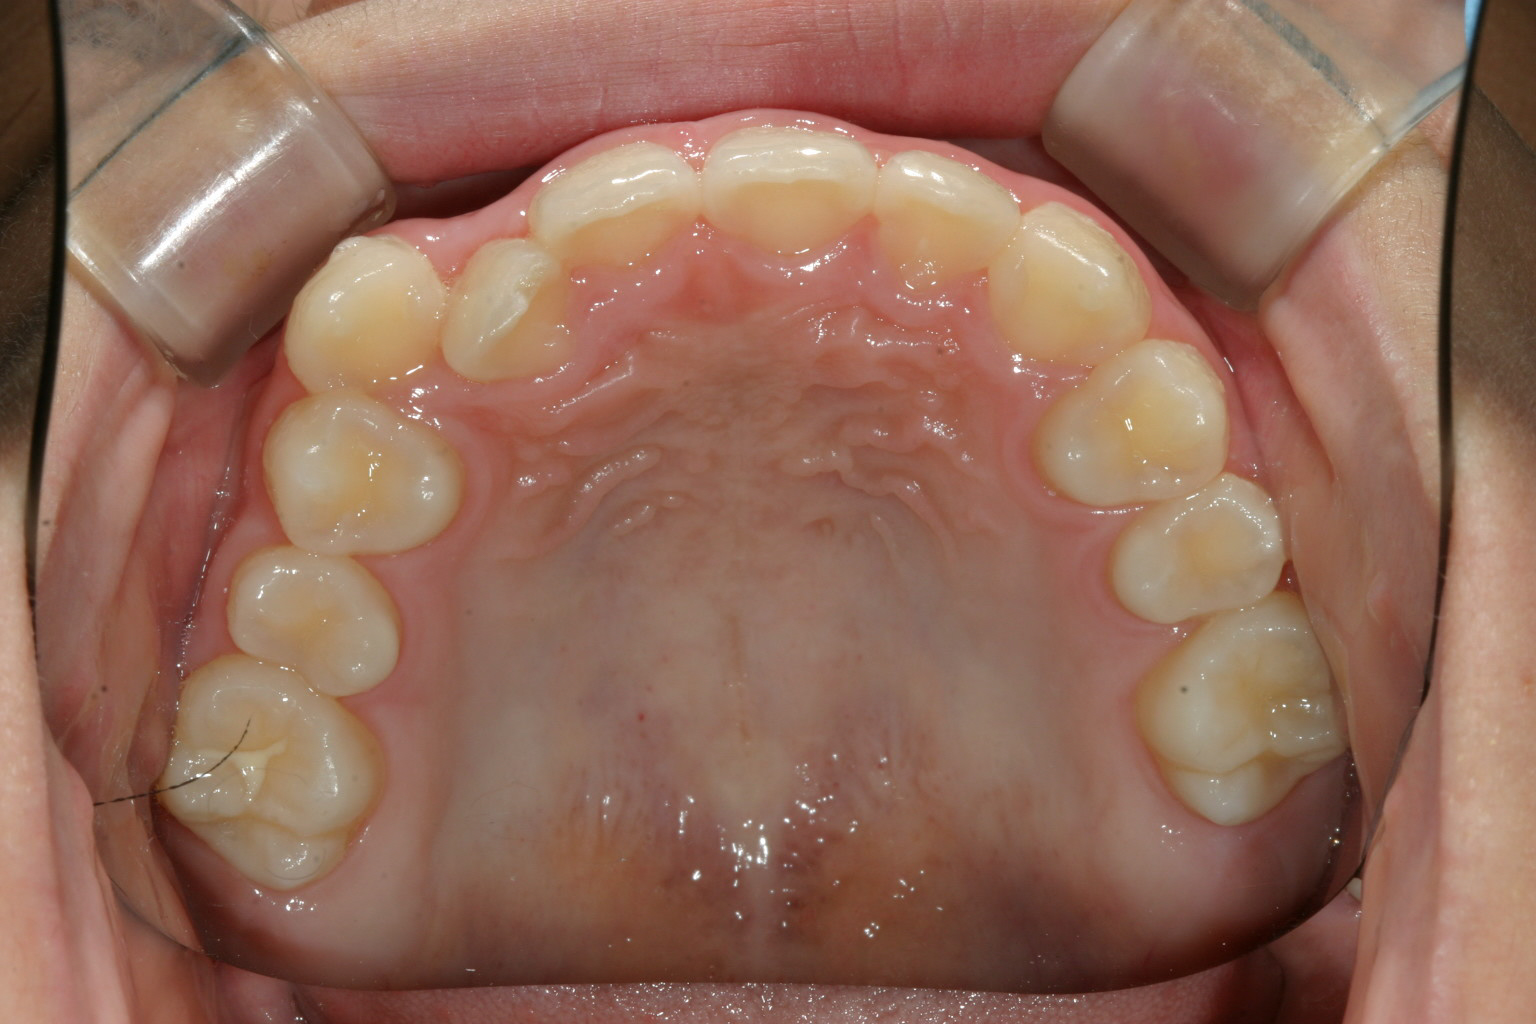

前歯部が内方に入ってます。

下顎は綺麗なアーチですね~

うけ口になってます。